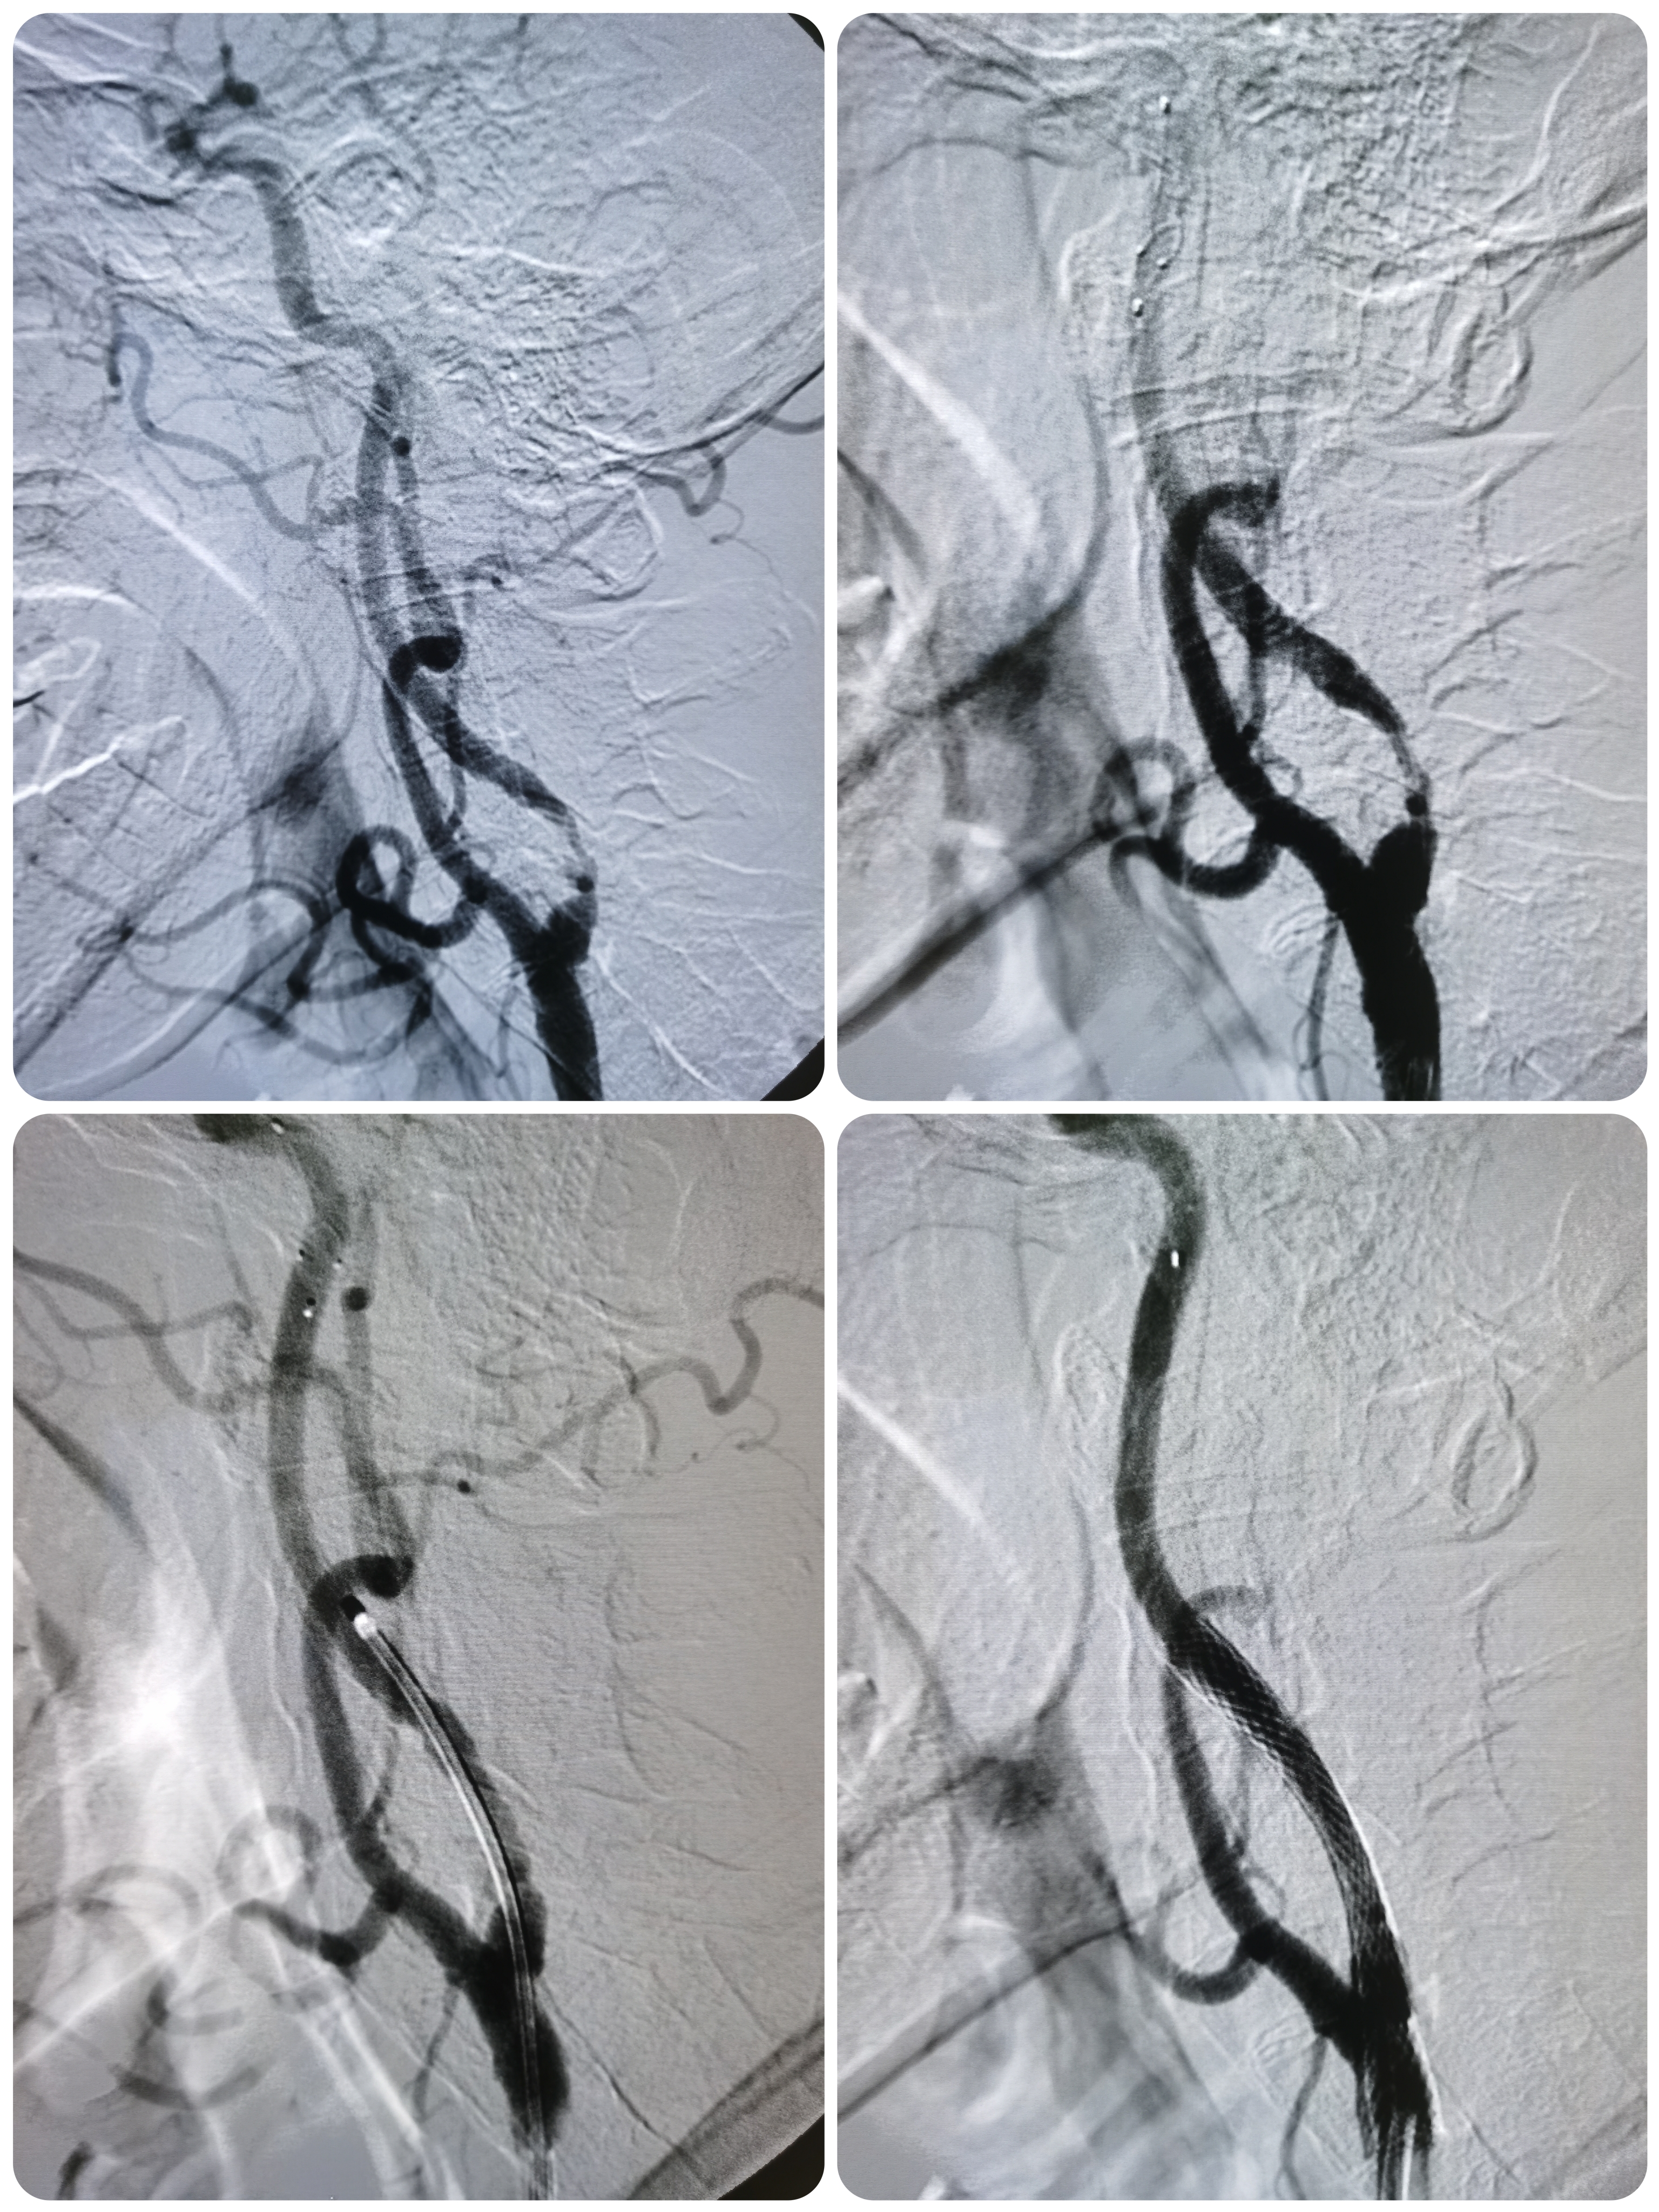

3型主动脉弓

右侧椎动脉颅外段正常

右椎颅内段纤细

左侧锁骨下动脉迂曲,左椎发育不良

右颈内动脉颅外段正常

右侧胚胎型大脑后动脉。

颅内段显影良好。

左侧颈内动脉起始部次全闭塞,局部斑块不稳定。

微导丝顺利通过病变后交换入远端保护伞

4/30球囊预扩后狭窄改善

9/40支架定位

支架释放后狭窄解除